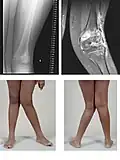

Set forfra danner lårknoglen (femur) og skinnebenet normalt en vinkel på 175° i forhold til hinanden. Folk der er kalveknæede har en mindre vinkel (genu valgum) og folk der er hjulbenede har en større vinkel (genu varum).

En kalveknæet mand.

Røntgenbillede af en to-årig med engelsk syge.- Real-time MRI af et knæ.